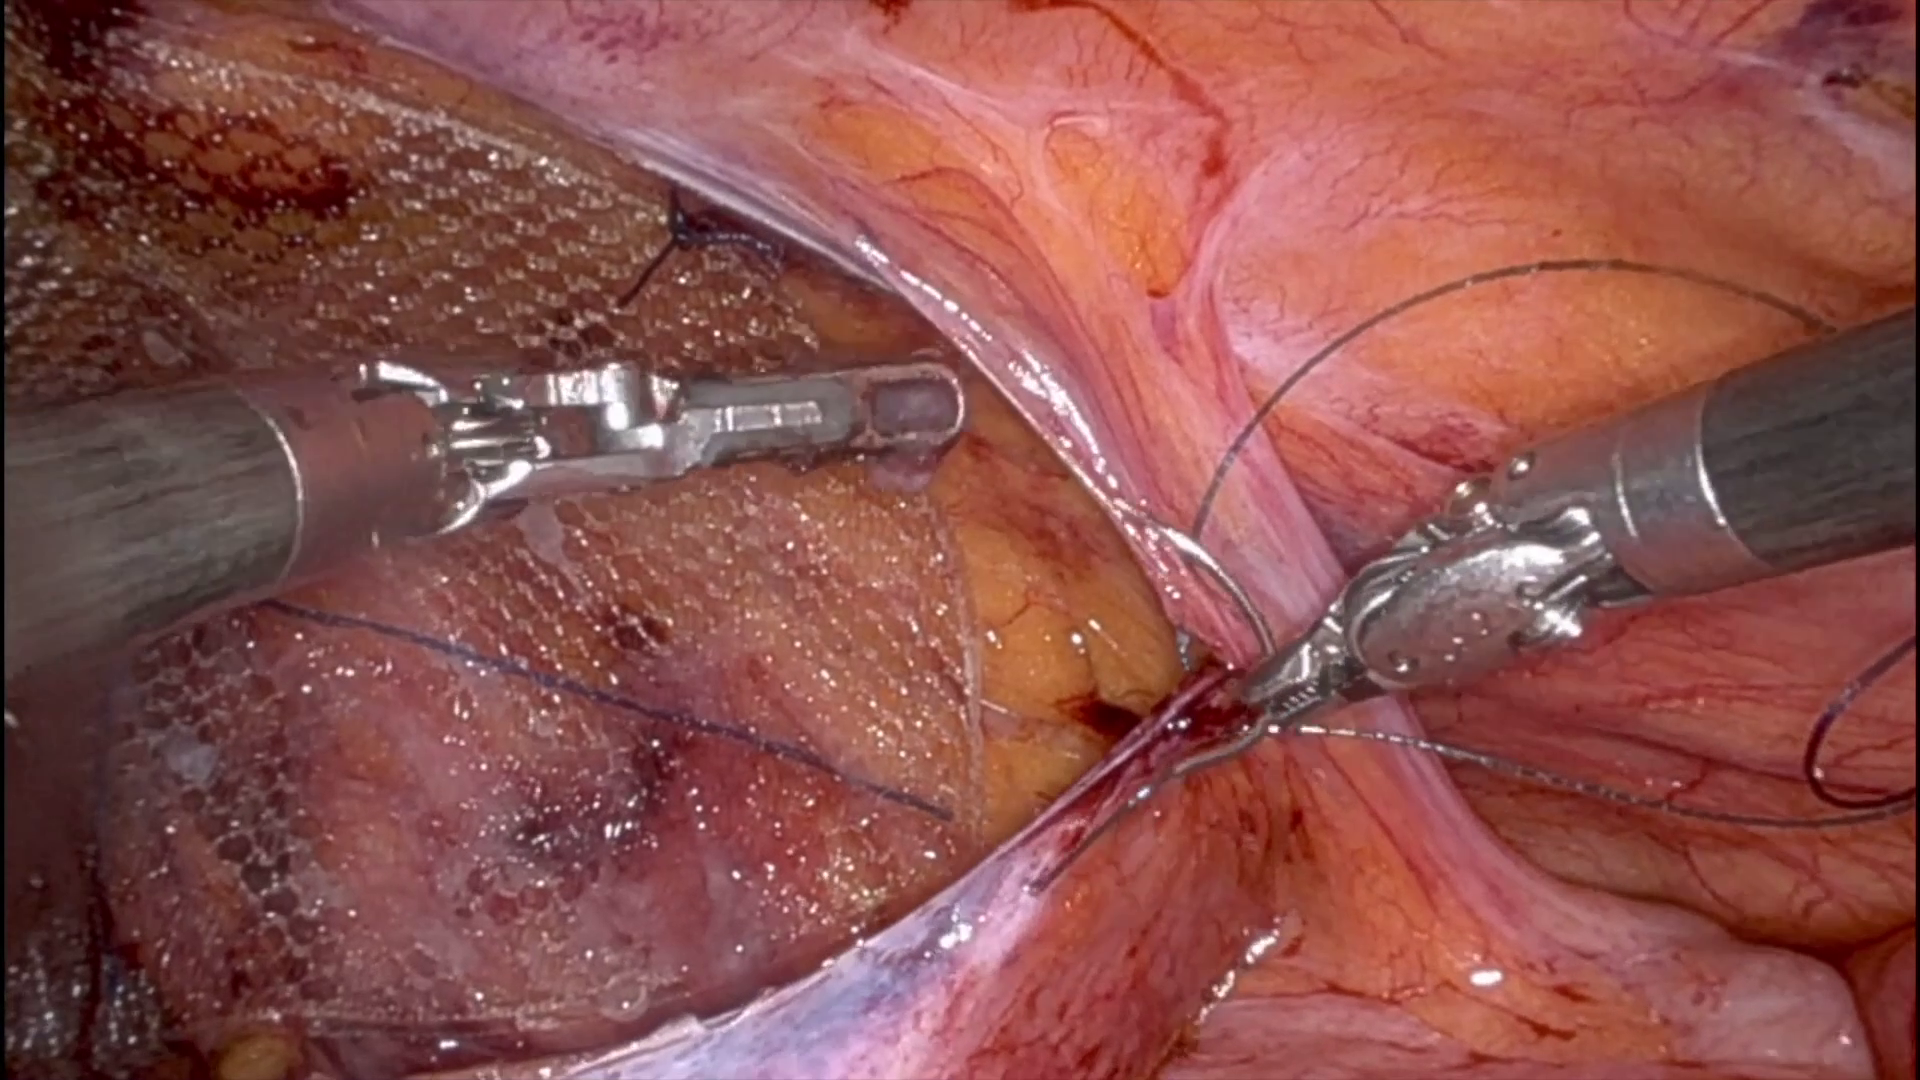

Dr. Malcher | Repair of a sliding right inguinal hernia containing the cecum

Repair of a sliding right inguinal hernia containing the cecum